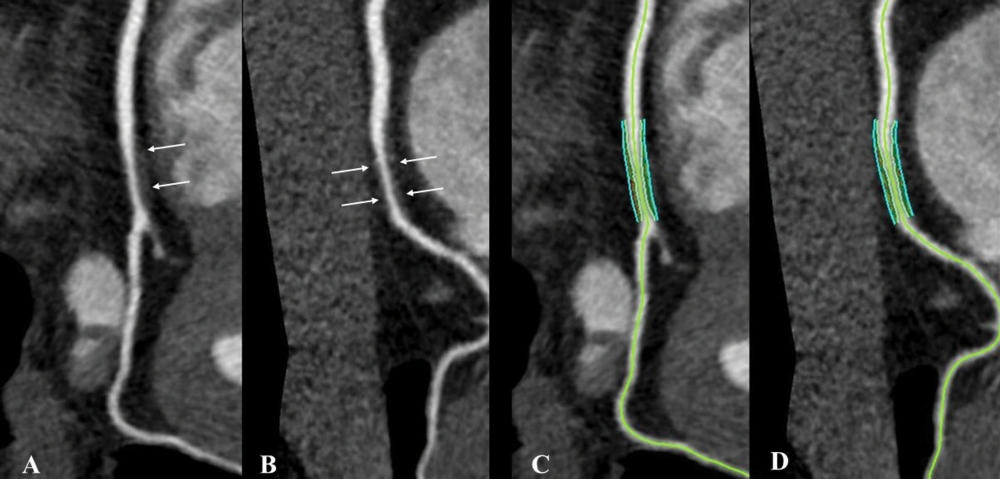

Figure 2. Noncalcified coronary plaque in an asymptomatic 52-year-old man living with HIV with a 10-year Framingham risk of 5%. Images show 256-section contrast-enhanced coronary CT angiography with electrocardiographic gating and curve reformat. A, B, CT scan shows a smooth noncalcified plaque in the right coronary artery (arrows) with 70%–80% stenosis. C, D, The right coronary artery plaque volume was 130 mm3 (cyan lines).